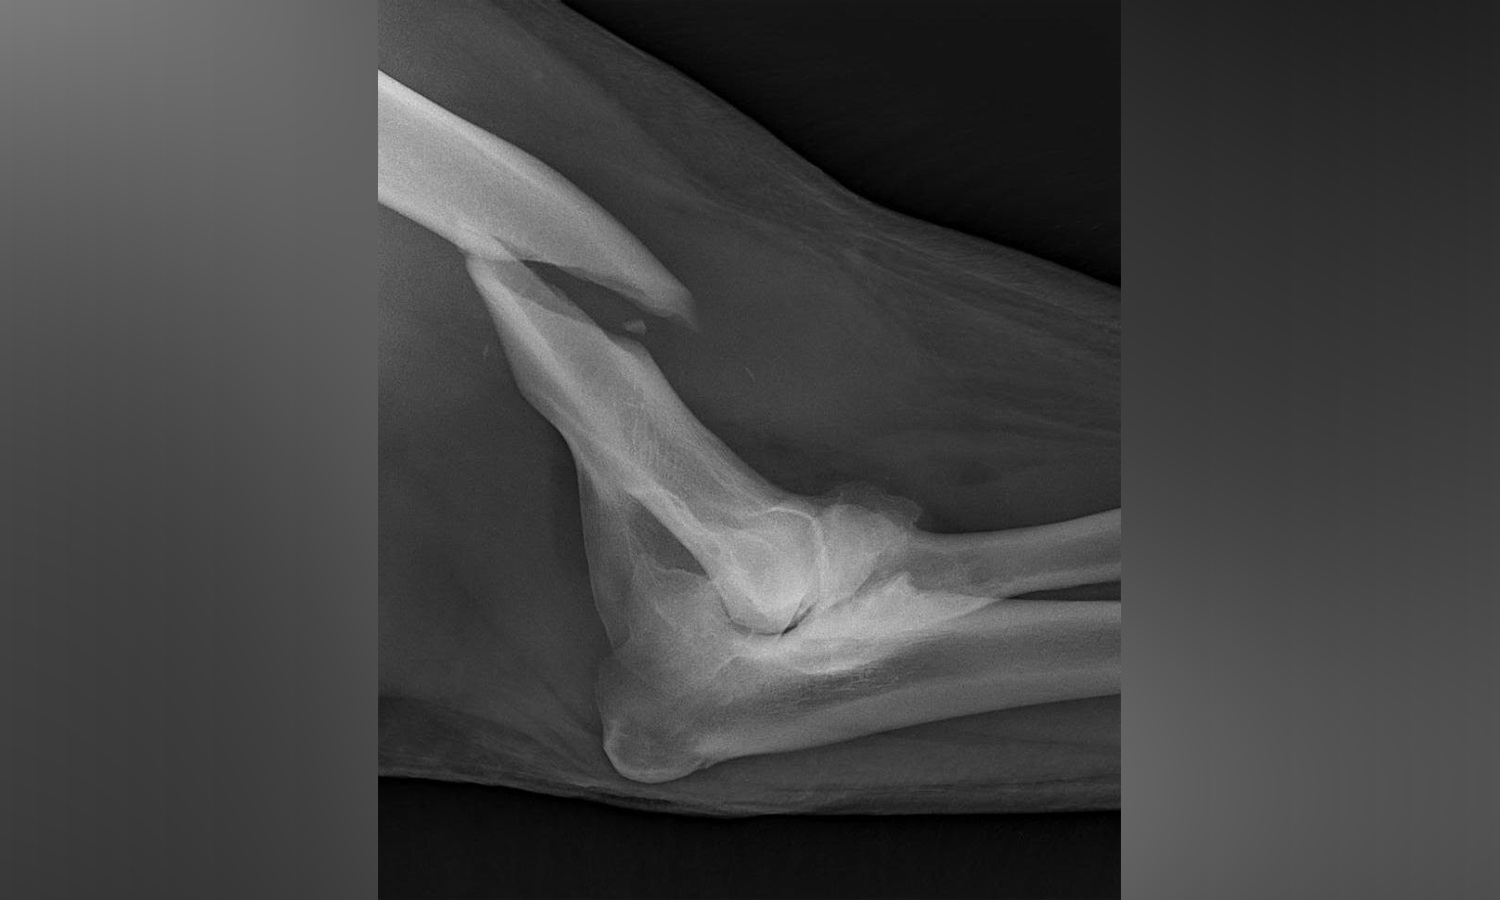

Zookeepers began to suspect something was wrong on Jan. 24 after the 3-year-old bear was unwilling to move in her enclosure, Hogle Zoo spokeswoman Erica Hansen said. X-rays taken on Sunday showed a break in her bone that runs from her shoulder to elbow.

The team will use plates, screws and pins to fix the break, zoo officials said. Nora will be assessed after the surgery, and could face more surgeries if the fixation breaks.